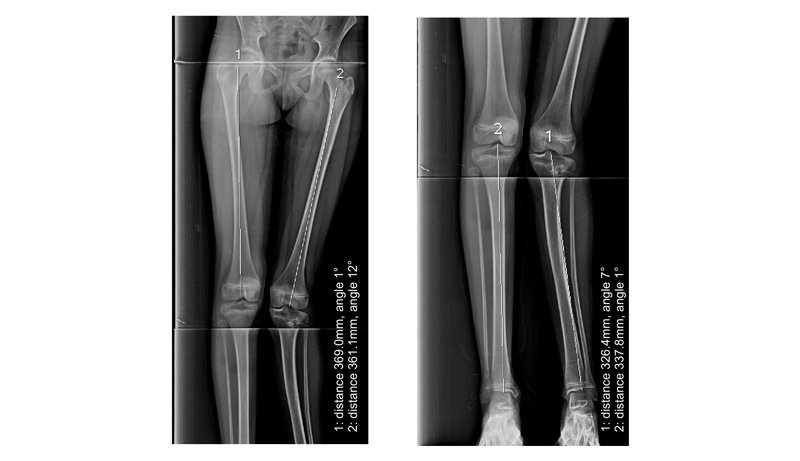

Full Length X-Ray

Indications

1 : For planning of any realignment operation of lower limb, mainly for genu valgus & varus deformity due to osteoarthritis / post # healing.

2 : To measure limb length discrepancy - congenital/acquired.